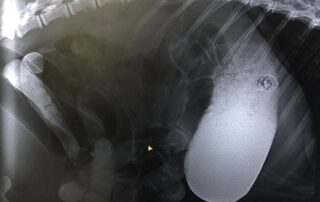

Der seltene Fall… Der verschluckte Pfirsichstein

Bei einem Minischwein konnte ein Pfirsichstein, der sich im Dünndarm direkt am Magenausgang festgesetzt hatte, entdeckt und erfolgreich durch eine Operation entfernt werden. Deshalb bitte aufpassen, gerade junge Tiere sind verspielt und verschlucken gern das Eine oder Andere….